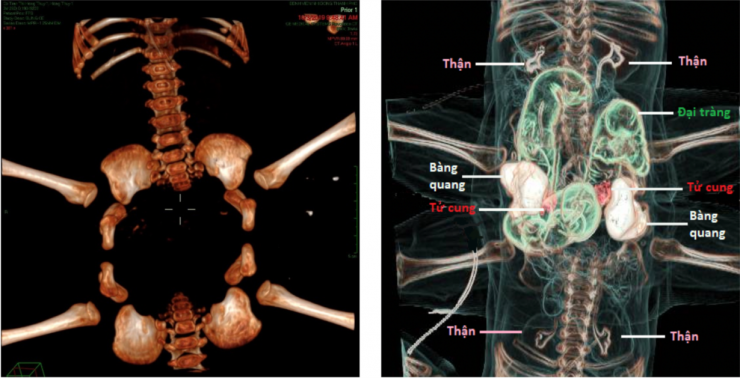

Với các phương tiện chẩn đoán hiện đại dành cho Nhi khoa như chụp cộng hưởng từ (MRI), Chụp vi tính cắt lớp mạch máu (CTA) các bác sĩ chẩn đoán hình ảnh của bệnh viện đã phát hiện hàng loạt các bất thường tại vùng bụng chung. Về hệ tiêu hóa: 2 bé có chung 1 phần hồi tràng, 1 khung đại tràng và chỉ có 1 lỗ hậu môn. Về hệ thận niệu: 2 bé có 2 bàng quang nằm 2 bên của ổ bụng chung, mỗi bàng quang được 2 niệu quản xuất phát từ 2 bé khác nhau đổ vào thay vì của cùng 1 bé. Về cơ quan sinh dục 2 bé có tử cung âm đạo đôi. Ngoài ra, 2 bé còn có hở khớp mu, khung chậu 2 bé lại xếp thành 1 vòng tròn.